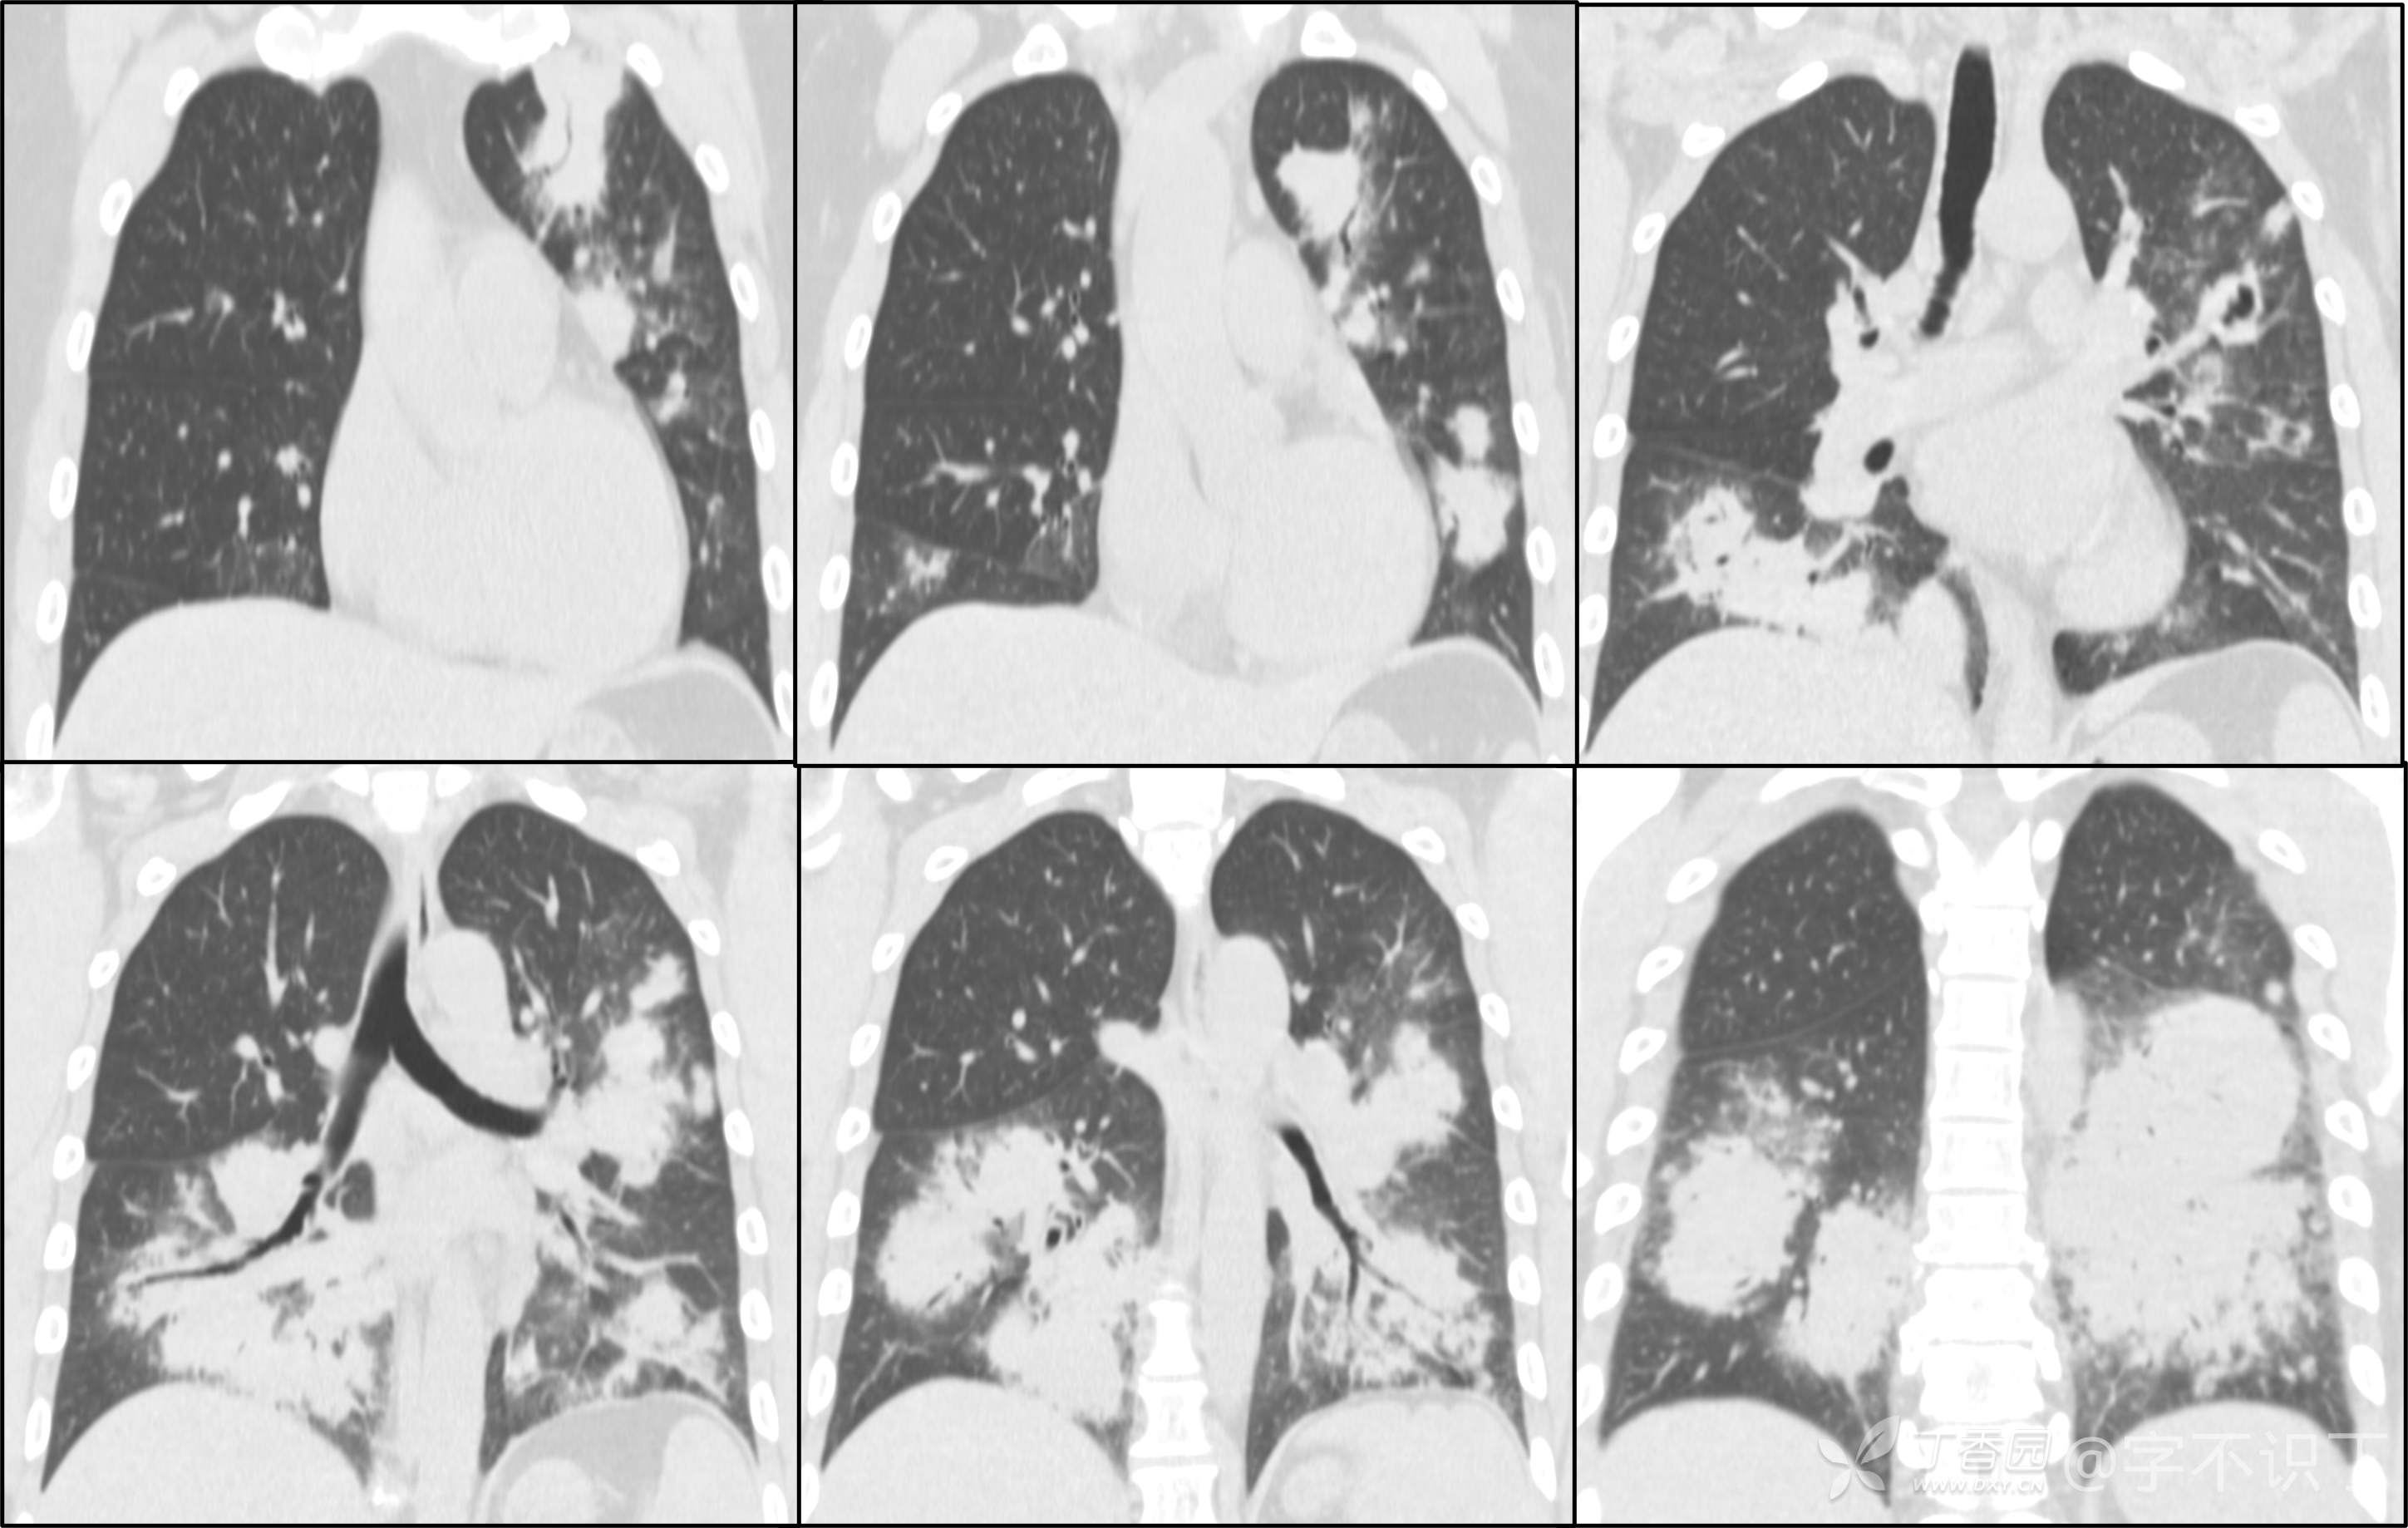

胸部病例讨论

患者性别:男

患者年龄:40岁

主诉:反复咳嗽2年,再发2月,咯血发热5天

简要病史:2年前无明显诱因出现阵发性干咳;2月前咳嗽症状较前加重,有少量白色粘液样痰,未经特殊处理,7天前咳嗽症状较前加重,伴咳黄脓样痰,痰中带血丝,予以哌拉西林舒巴坦+莫西沙星抗感染及祛痰等对症支持治疗,未觉好转,予以拉氧头孢、左氧氟沙星、布洛芬、氨溴索等对症处理,咳嗽、咳痰症状未缓解,仍有发热

体格检查:曾从事装修等工作,近半年从事煤矿管理工作。近期饮酒较频繁。既往有冶游史。

辅助检查:血液病原菌培养、分枝杆菌涂片检查、真菌涂片检查、一般细菌涂片检查、痰培养均阴性